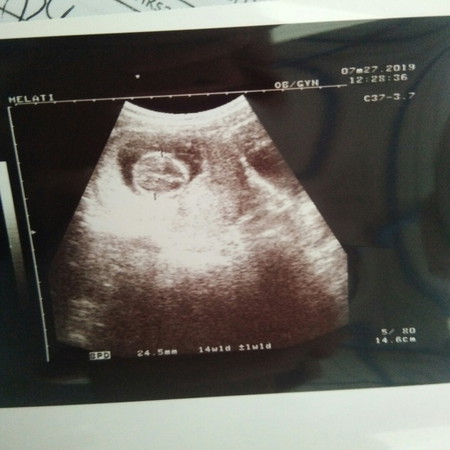

USG

Bun aku tadi Usg karna rame banget antrian dokternya jg buru2 kesel jg si bun pdahal aku udh siapin banyak pertanyaan ?? Dokternya bilang babynya sehat dan semuanya bagus, itu jg karna aku nanya gimna dok babynya? Nahh menurut bun itu yg bulet kepala baby nya kah? Dan bun yg tau mohon jelasi hasil Usg nya bun ? soalnya itu gambar usg nya kurang jelas ???